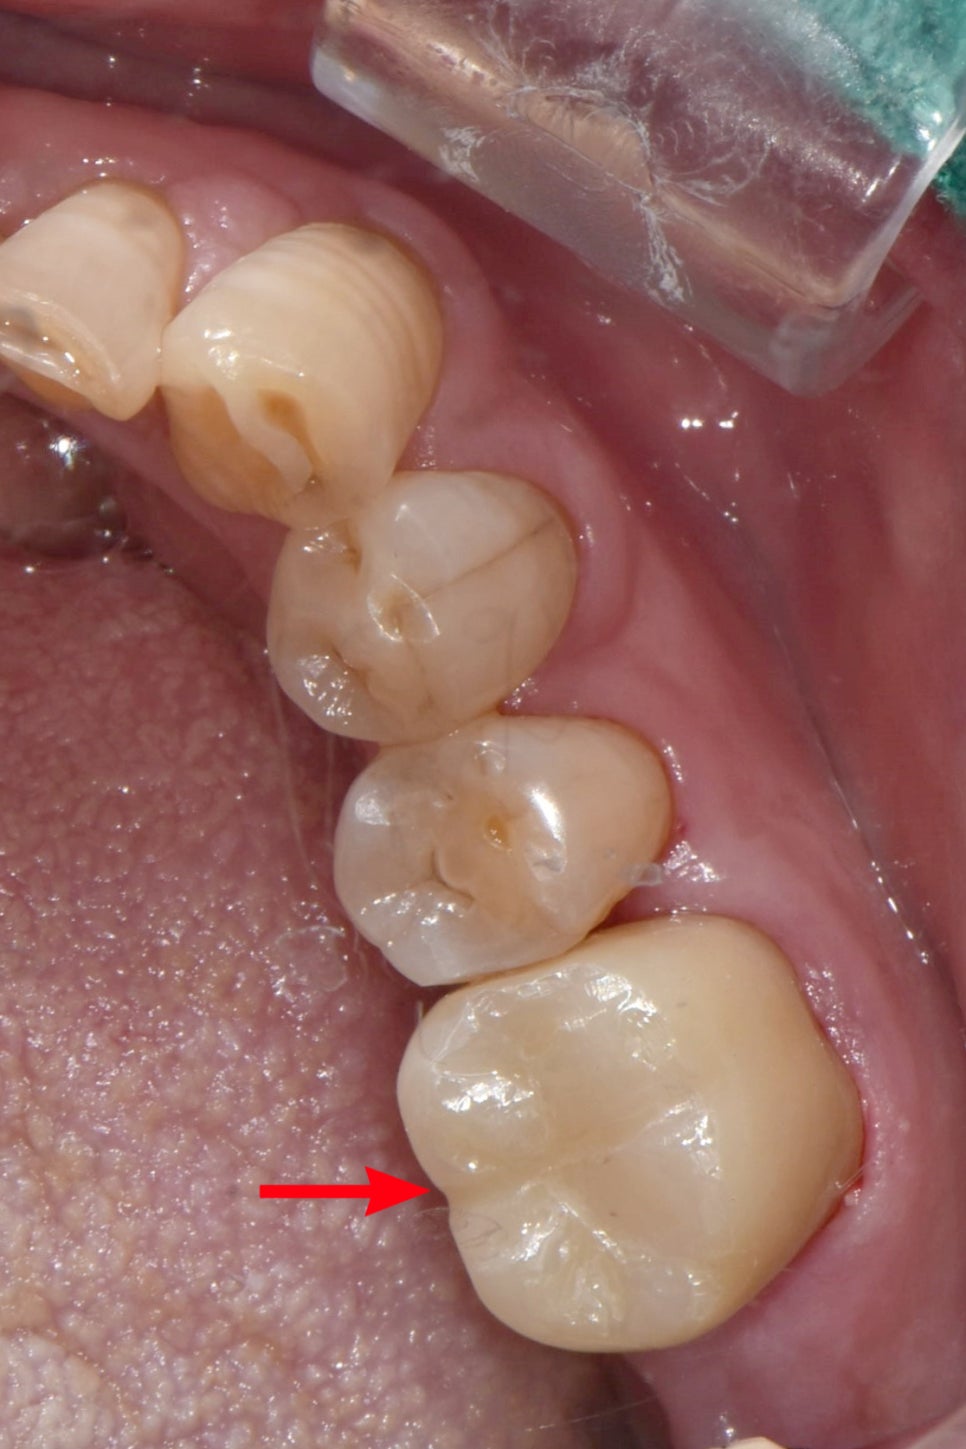

구강내사진과 엑스레이를 찍어보았는데요.

보통 인접면 충치의 경우 인레이 치료를 많이 하는데,

이 경우는,

1.교합면을 포함한 여러면의 치아가 썩었다는 점

2. 앞치아와 공간이 생겨 헐거운 점

3. 교합면을 포함해 다른 부분에도 충치가 있다는점.

을 고려하여

크라운 치료로 진행하기로 합니다!!